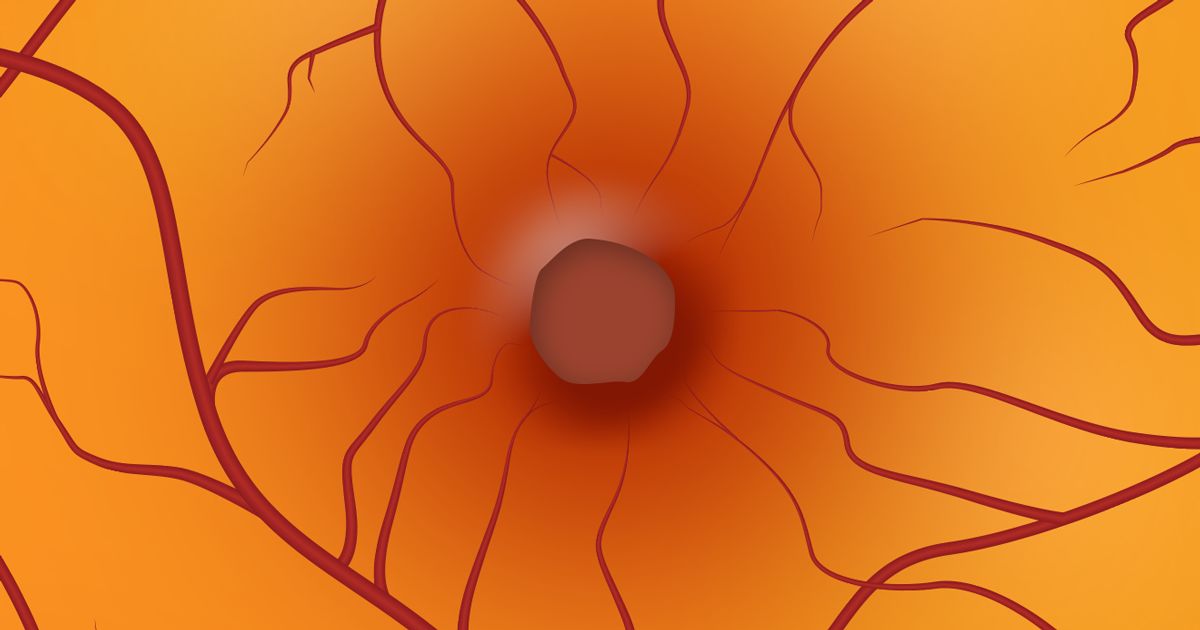

La mácula (o mácula lútea) es un punto muy pequeño en el centro de la retina. Desde el punto de vista visual, es la parte más sensible de la retina. La mácula es responsable de la agudeza visual, la visión central detallada (para leer, conducir y reconocer rostros, por ejemplo) y la visión de los colores.

La mácula está llena de células sensibles a la luz llamadas conos. El resto de la retina está formado principalmente por células fotosensibles llamadas bastones. Los bastones "ven" sombras en gris y negro, detectan movimiento y son responsables de la visión periférica.

Un agujero macular es una pequeña ruptura en la mácula que causa una visión central borrosa y distorsionada que generalmente ocurre de repente.

Debido a que el vítreo está adherido a la retina con pequeñas hebras de colágeno (una proteína común en el cuerpo), estas hebras de colágeno pueden tirar de la retina a medida que el vítreo se vuelve líquido. A veces, esto puede arrancar una pequeña parte de la retina y causar un agujero. Si este trozo de retina está en la mácula, se llama agujero macular.

Otra forma en que pueden ocurrir los agujeros maculares debido a cambios en el vítreo es cuando las hebras de colágeno dentro del vítreo permanecen adheridas a la retina y se desprenden del vítreo líquido. Estas hebras pueden contraerse alrededor de la mácula, lo que hace que la mácula desarrolle un agujero debido a la tracción.